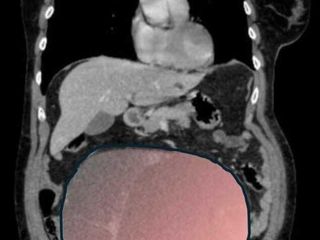

Per mesi la gigantesca cisti ovarica, con un diametro di circa 28 centimetri, è rimasta nascosta, senza dare segnali evidenti. La paziente non si era accorta di nulla. L’allarme è scattato quando la massa, associata alla presenza di una seconda neoplasia intestinale, ha iniziato a comprimere il colon, provocando sintomi acuti ed improvvisi fino ad una grave difficoltà intestinale non più ignorabile.

Durante l’intervento emerge tutta la gravità della situazione. La gigantesca neoplasia ovarica viene asportata: pesa circa 6 chilogrammi, con un volume paragonabile a quello di una gravidanza gemellare a termine. Ma non è l’unica minaccia. I sintomi più pericolosi sono legati alla sofferenza intestinale, che richiede un intervento immediato e coordinato di più specialisti.